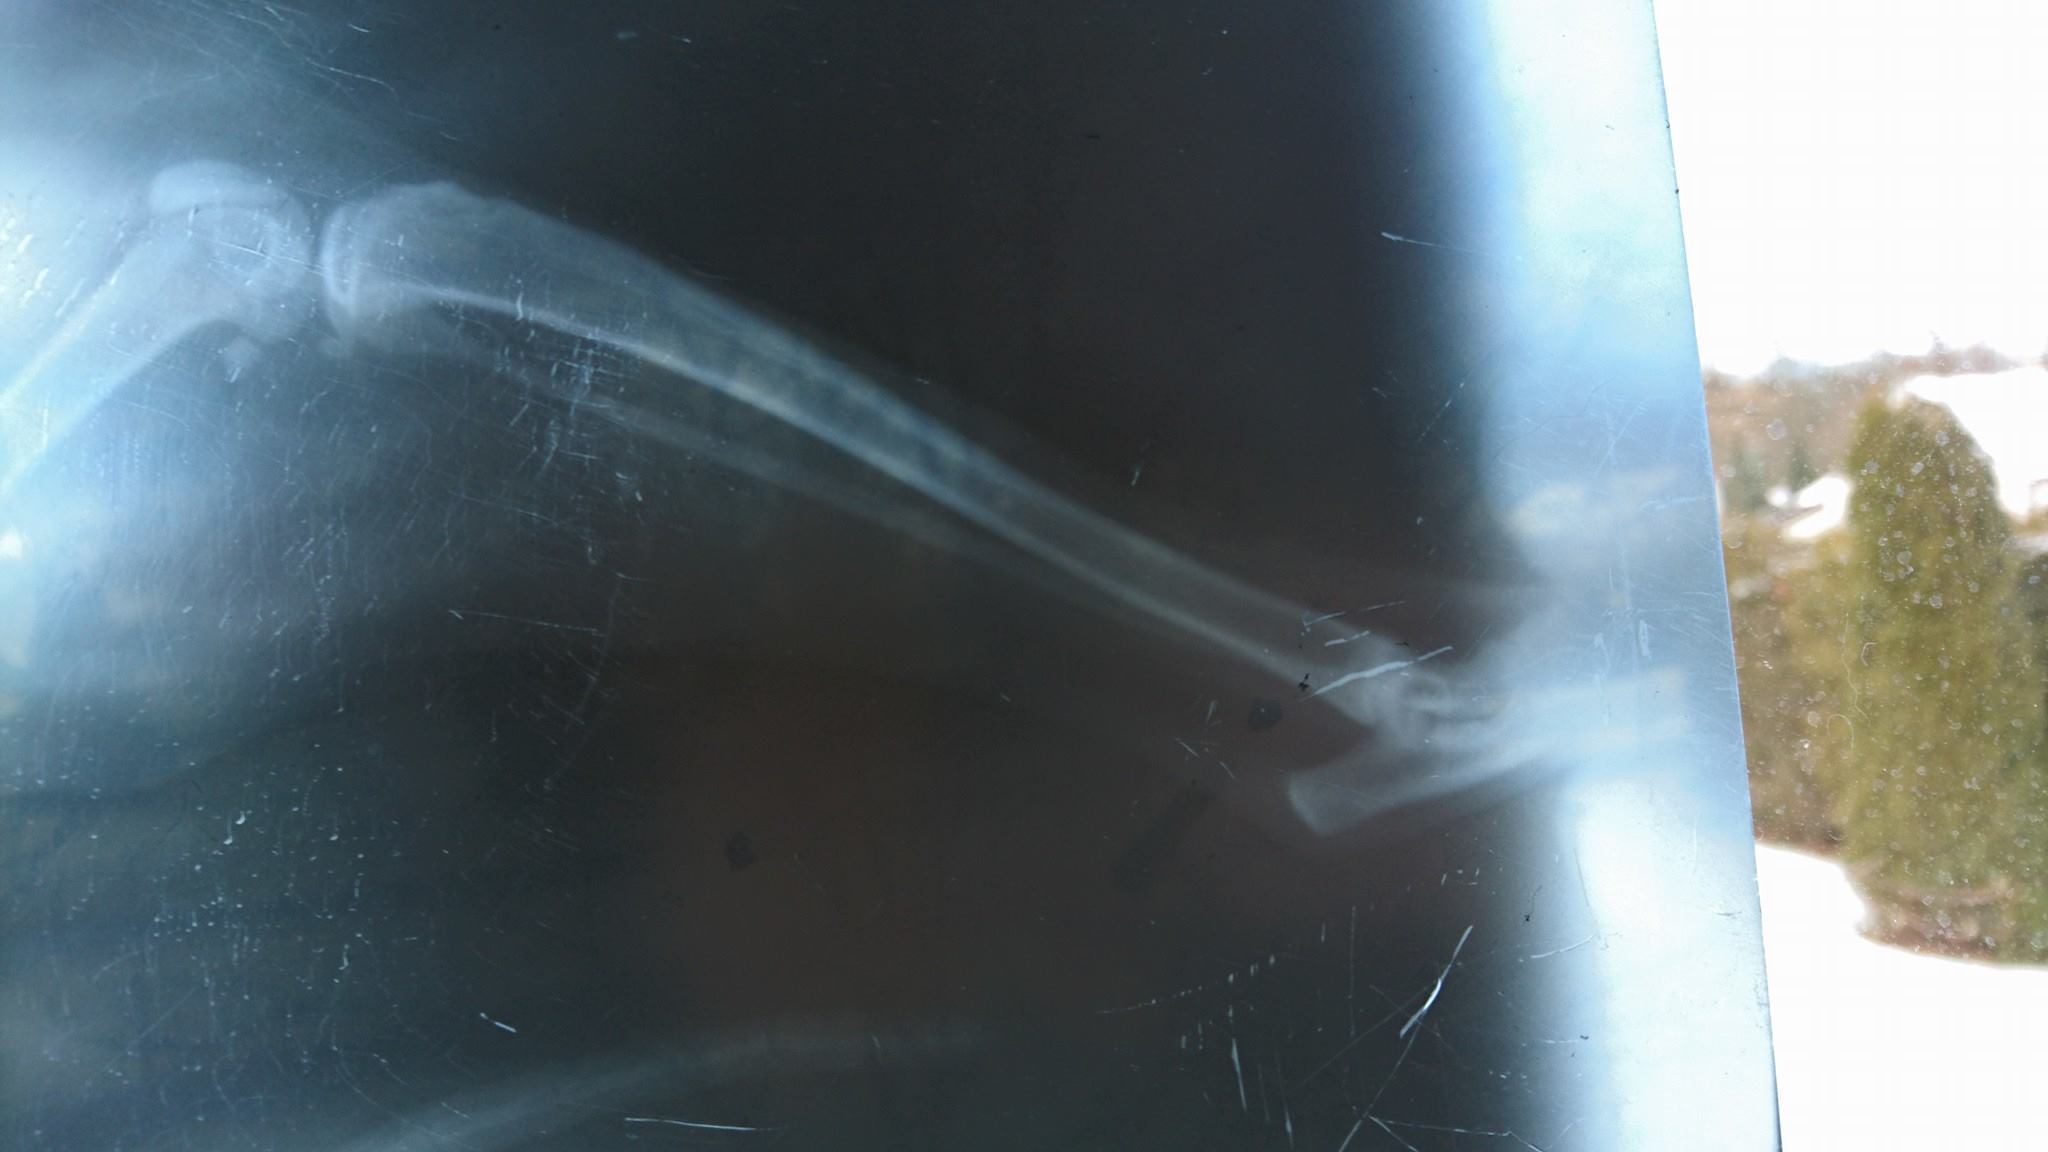

Bílomourovatá kočička s delší srstí. Nalezli ji rodiče Sluníčkového Kajetánka na své zahradě, hubenou a se zlomenou nožičkou. Kočička je nenechala chladnými a byla dopravena na veterinu a následně do Sluníčka. Nyní je kočička hospitalizovaná v Mělníku na klinice a je zřejmě po operaci. Zadní nožička ji plandala, stehenní kost byla přelomená. Kosti se musí k sobě sešroubovat, ale musí to být čerstvé zranění.